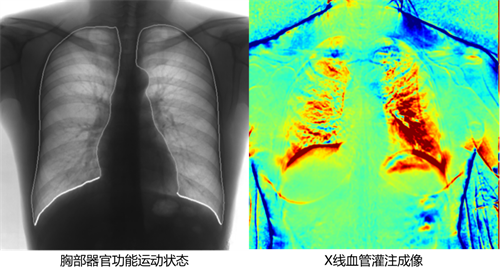

不同于常规静态DR只能进行平片摄影检查,动态DR可以实现多模态的检查。包括数字化摄影、数字化透视、数字化造影、可视化点片、尘肺筛查、断层融合功能检查、DSA功能检查、全脊柱及双下肢拼接检查、动态功能成像等多模态检查,相较于静态DR具有更加丰富的临床应用。不止可以应用于放射科,还可以应用于体检科、内科、外科、骨科、急诊科等,应用的科室更加广泛。

动态DR是所有新技术应用的生态平台,相比静态DR拥有更加广阔的发展空间和更加前沿的新技术,现在包括GE、西门子、安健科技等各大行业顶尖医疗器械公司都在往动态DR上的发展,所有DR的新技术,包括能谱技术、动态功能化成像技术、WR-3D负重位锥形束CT摄影、断层融合扫描摄影等都需要动态DR作为基础,而这些新技术早已经在医疗检查中不可或缺,并且得到医院的一致认可,而静态DR则无法支撑以上新技术。